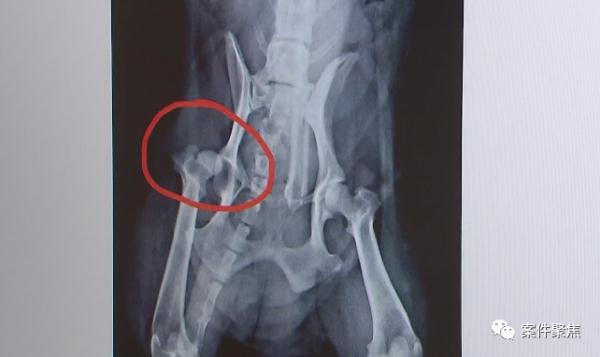

有目击“狗咬狗”过程的一位路人表示,金毛犬在拼命地咬泰迪犬,泰迪犬受伤后出血,自己当时跑过去发现,泰迪犬的肚子上被直接咬出个洞。

为了治疗泰迪犬,郝女士花费了3万余元医疗费,然而,赔偿费用协商不成,两位犬只主人只能对簿公堂。